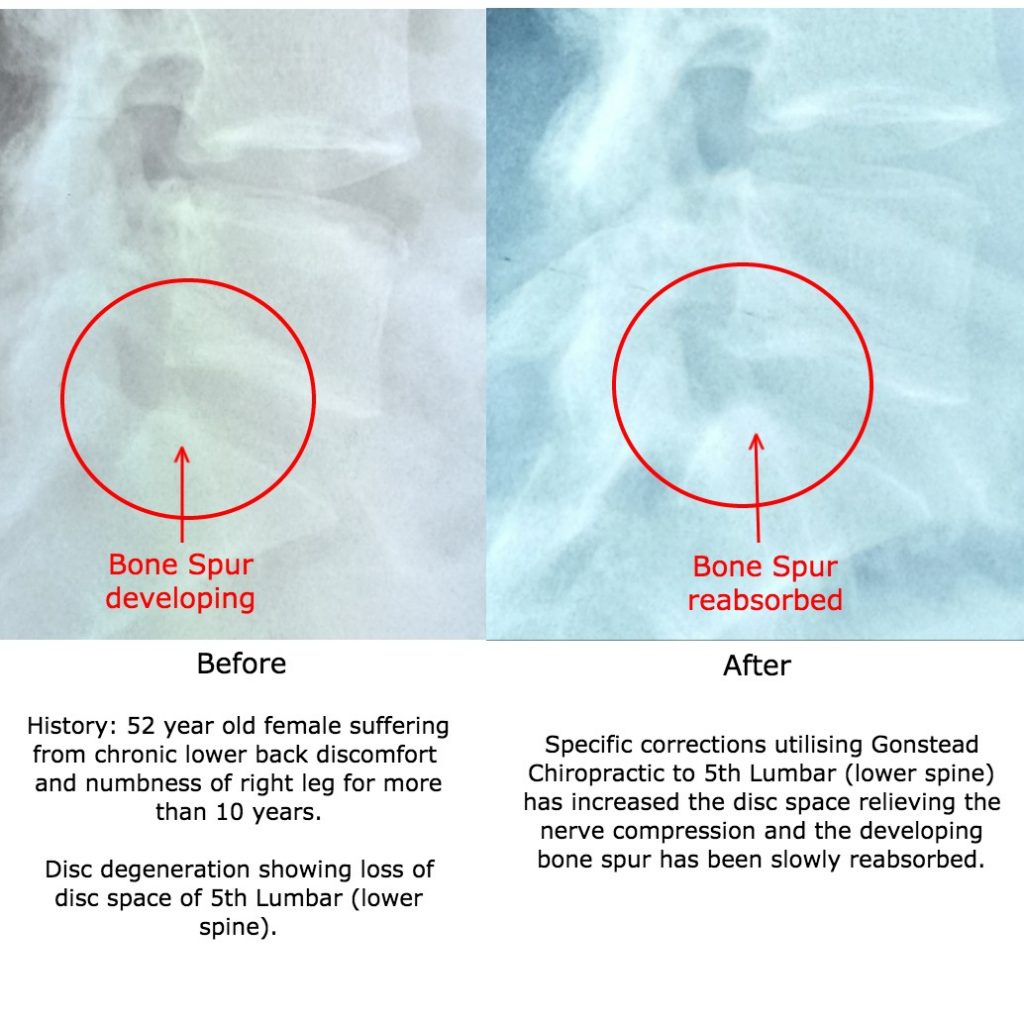

Development of bone spur due to 5th Lumbar Disc Degeneration – A …